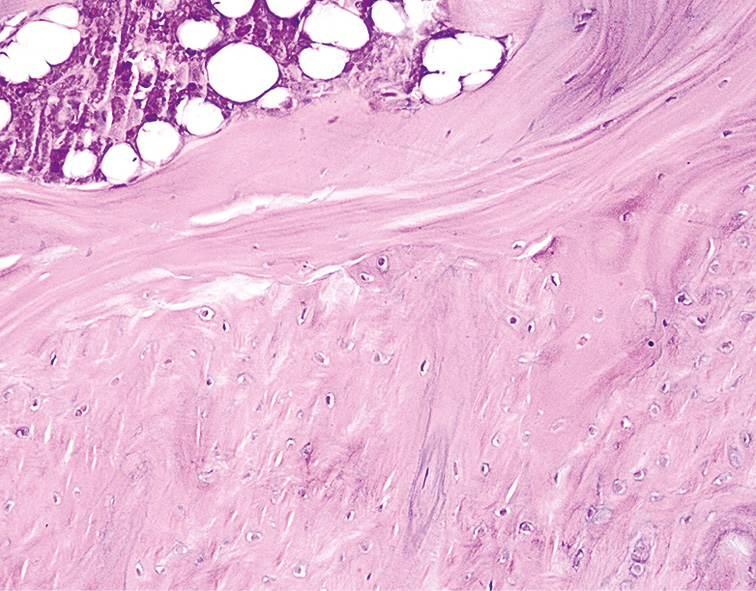

Проведенные гистологические исследования СОП животных опытной группы через 7 мес после ДМГ поражения позволили выявить глубокие деструктивно-дегенеративные изменения всех ее компонентов. Так, среди фрагментов гиалиново-волокнистой хрящевой ткани отмечались скопления фиброретикулярных клеток костного мозга с примесью жировых включений, а также опухолевые клетки (рис. 7). В этот же срок эксперимента для тканей СОП животных были характерны элементы костного мозга в прослойках хрящевой ткани, что приводило к утолщению стромальной соединительной ткани и фиброзу (рис. 8).

Рис. 7. Слизистая оболочка пасти животного (опытная группа) через 7 мес от начала эксперимента. Окраска гематоксилином и эозином, ×280.

Fig. 7. The mucous membrane of the animal’s mouth (experimental group). after 7 months from the beginning of the experiment. Staining with hematoxylin and eosin, ×280.

Рис. 8. Слизистая оболочка пасти животного (опытная группа) через 7 мес от начала эксперимента. Окраска гематоксилином и эозином, ×180

Fig. 8. The mucous membrane of the animal’s mouth (experimental group). after 7 months from the beginning of the experiment. Staining with hematoxylin and eosin, ×180.